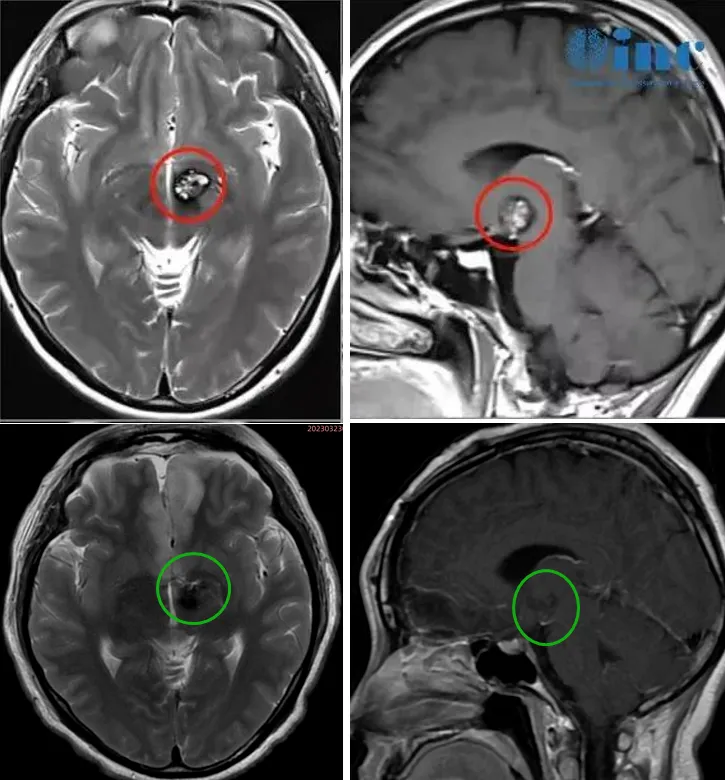

30岁的文文罹患丘脑基底节海绵状血管瘤,经历多次出血。治疗选择从保守到药物,无法有效缓解症状。症状甚至不断加重,右眼视力下降明显,右下肢无力,步态不稳,复查MRI提示病变增大。但是医生考虑手术并发症和风险过大,还是建议保守治疗。然而多次出血已经无法保守治疗。通过INC远程咨询巴教授之后,巴教授表示:畸形位于大脑的一个关键区域,但对我来说是可以做手术的。由于反复的出血和病人年龄较年轻,是有手术指征,手术也是可行的。北京时间2023年3月23日,文文成功手术。手术难度堪比脑干,早在30年前巴教授已有成功案例发表!

术前术后影像对比